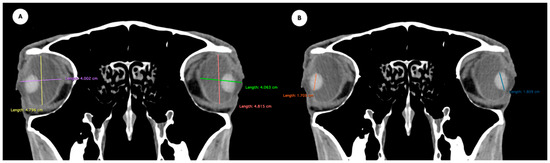

Figure 4.

Parasagittal multiplanar reconstruction (MPR) images of the equine eyeball showing (A) eyeball length and (B) the maximal antero-posterior distance of the lens measured along its midline.

Table 1 provides summary statistics (mean, median, range, and standard deviation) for the internal ocular measurements of the left eye, right eye, and both eyes combined across all 20 horses. The average ocular measurements indicated that the eyeball height (5.19 ± 0.13 cm) was greater than its width (4.28 ± 0.12 cm), confirming the characteristic oval shape of the equine eye. The mean axial length was 5.09 ± 0.17 cm, consistent with previous descriptions of large-globe morphology in horses. The orbital cavity measured 5.27 ± 0.12 cm in height and 6.29 ± 0.14 cm in length. The anterior and posterior chambers had mean widths of 0.56 ± 0.07 cm and 2.26 ± 0.09 cm, respectively. The lens exhibited a mean height of 1.53 ± 0.06 cm, width of 1.23 ± 0.06 cm, and length of 1.63 ± 0.04 cm. These results collectively reflect the regular proportions and bilateral symmetry of the equine eyeball and its internal structures, as detailed in Table 1. The Mann–Whitney U test revealed no statistically significant differences in the measurements between the right and left eyes. Similarly, when all variables were considered collectively, the analysis confirmed the absence of significant differences between both eyes